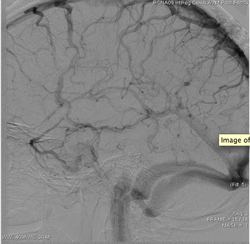

Vascular imaging was revolutionized in the 1980s with the development of DSA. The technique involves injecting a contrast dye into the vascular network while taking a rapid series of X-ray images. The first image, taken before the dye arrives in the field of view, is made into a mask image that is digitally removed, or “subtracted,” from the images showing contrast. The resulting images, which show only the contrast in the vessels, are used to display a 2-D view of the vessels. Because the contrast is traveling through the vessels with the flow of blood, the arteries, capillary circulation, and then the veins are imaged in a DSA series. When used with today’s modern digital flat panel X-ray detectors, DSA produces excellent images of vascular anatomy over time.

AngioViz provides a new visualization of the vascular flow seen in DSA imaging, utilizing a technique called parametric imaging. AngioViz looks at each pixel in the image series and determines two things — the peak value of opacification caused by the contrast, and the time it takes for that pixel to reach peak opacification. These two parameters can be displayed as separate images or combined into a single color-coded image that represents parameters of vascular flow. This enables doctors to perceive parameters of flow quickly to support decision-making. In addition, AngioViz allows easy comparison of parametric images from different DSA acquisitions, such as pre- and post-treatment images. This can help physicians understand the impact on flow dynamics of various interventional treatments.